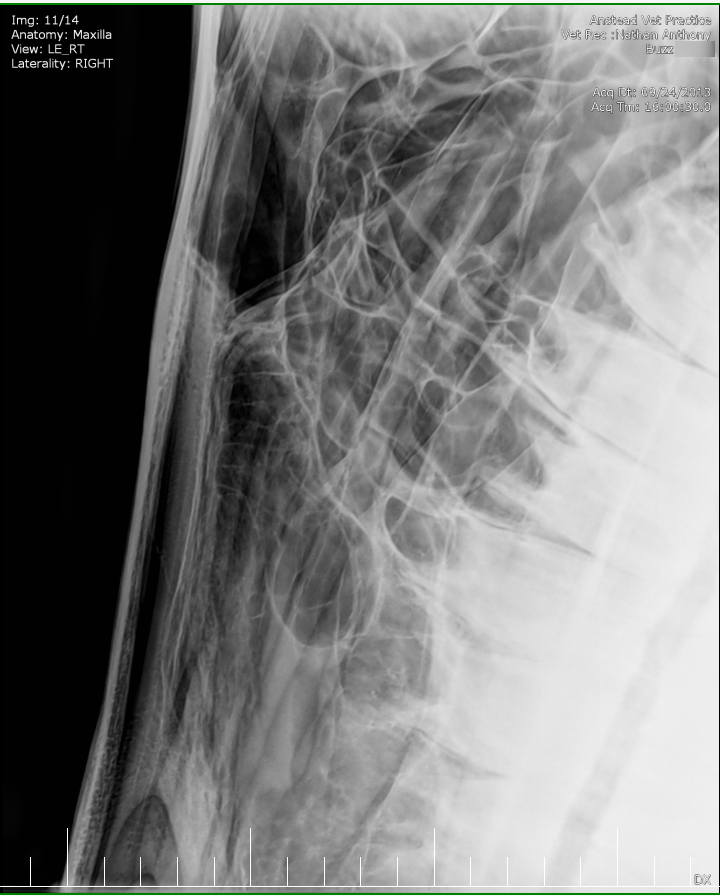

Posted on Sunday, May 8, 2016 - 6:24 pm: Thank you for the welcome!I did contact the lab to see if they still had the samples but they will only speak to the vets who submitted the samples. I've asked my vet to ask on my behalf but haven't yet heard back yet. The horse has been scoped and I was told that it all looked normal. The stylohoid bone and guttural pouches normal. The inflammation is mostly around the nostrils as per the pic but there are a couple of small spots further up inside the nose. He's also had his skull xrayed which I'm told also looked normal. I've included the pics at the bottom. I've included a list of other things here that have been tested to see if they influence the shaking or inflammation for the better or worse: - experimental course of Equity - Flixotide via inhaler - high dose of prednisolone - did work! - low dose of prednisolone - did not work - teeth checked by two different vet dentists - fly masks & nose nets - relocated him to several different places in the city incase it's an environmental allergen - all sorts of feed supplements - removed all hard feed, just feeding hay - stabled him 24/7 and fed him Haygain steamed hay incase it was something in the paddock - light/dark makes no difference to the shaking - it's not seasonal, happens year round I've also had bloodwork done and it showed a low red blood cell count. The blood was taken two weeks after the biopsies. My vet didn't think the low count was attributed to the blood loss from the biopsies so he suggested parasites but a worm count came back clean. I also had a test to see if there was blood in the manure, but nothing was found. There was no plan made to address the low RBC. Results are attached in a text file to maintain the spacing.

Xray images: